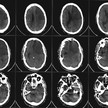

Neurologen haben wachsende Hinweise auf einen Zusammenhang zwischen Schlafstörungen und Schlaganfall. „Wir wissen seit ein paar Jahren, dass Schlafstörungen ein... Mehr»